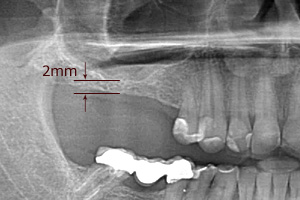

Jest to zabieg, mający na celu zwiększenie ilości tkanki kostnej w tylnym odcinku szczęki, co odbywa się poprzez zredukowanie objętości zatoki szczękowej. Nierzadko, wskutek zaniku kości będącego naturalną konsekwencją utraty zęba (lub zębów) z powodu choroby próchnicowej, periodontopatii lub urazów, objętość pozostałej kości jest niewystarczająca do uzupełnienia braków zębowych za pomocą wszczepów śródkostnych (implantów). Niedobór kości w tylnych rejonach szczęki spowodowany jest też stale trwającym procesem pneumatyzacji kości.

W metodzie z wypreparowaniem okna bocznego jesteśmy w stanie uzyskać nawet do 10mm nowej, świeżo utkanej tkanki kostnej, jednak przed wprowadzeniem implantu, wymagane jest odczekanie około 6-9 miesięcy w celu uzyskania przebudowanej, uformowanej nowej kości zdolnej do przyjęcia wszczepu. Niekiedy istnieje możliwość jednoczasowej implantacji wraz z zabiegiem podniesienia dna zatoki przy korzystnych relacjach ilości własnej kości do kości nowo tworzonej po zabiegu podniesienia dna zatoki. Postępowanie takie pozwala przyspieszyć zakończenie leczenia o okres późniejszego oczekiwania na osteointegrację implantu.